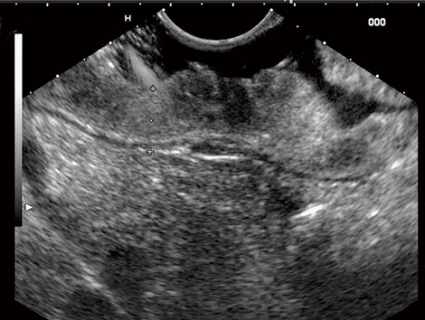

Submukösa tumörer

Submukösa processer är relativt ovanliga och orsakar sällan symtom. De upptäcks hos cirka 0,4 procent av patienter som genomgår rutinmässig gastroskopi. Ett vanligt problem med submukösa processer är att vanlig mukosabiopsi inte ger diagnostisk information. Endoskopiskt ultraljud är förstahandsmetod för att bedöma submukösa tumörer med avseende på storlek, vilket vägglager tumören utgår ifrån, ekogenitet och kanter samt för att differentiera mot extraintestinala inbuktningar. En av de viktigaste uppgifterna är att definiera vilket vägglager processen utgår ifrån (Figur 3).

Även om det ultraljudsmässiga utseendet är mycket användbart för att bedöma submukosala tumörer, finns det fall där finnålsaspiration eller vävnadsbiopsi kan vara avgörande för säker diagnos. En studie har visat att korrelationen mellan ultraljudsmässig bedömning och slutgiltig patologi är cirka 80 procent, och det diagnostiska utfallet av finnålsaspiration eller vävnadsbiopsi är mellan 80 och 90 procent [2, 3]. Endoskopiskt ultraljud kan ge vägledning för beslut om huruvida endoskopisk resektion är möjlig. Om förändringen engagerar muscularis propria eller djupare brukar man vanligtvis inte göra endoskopisk resektion på grund av risken för perforation.